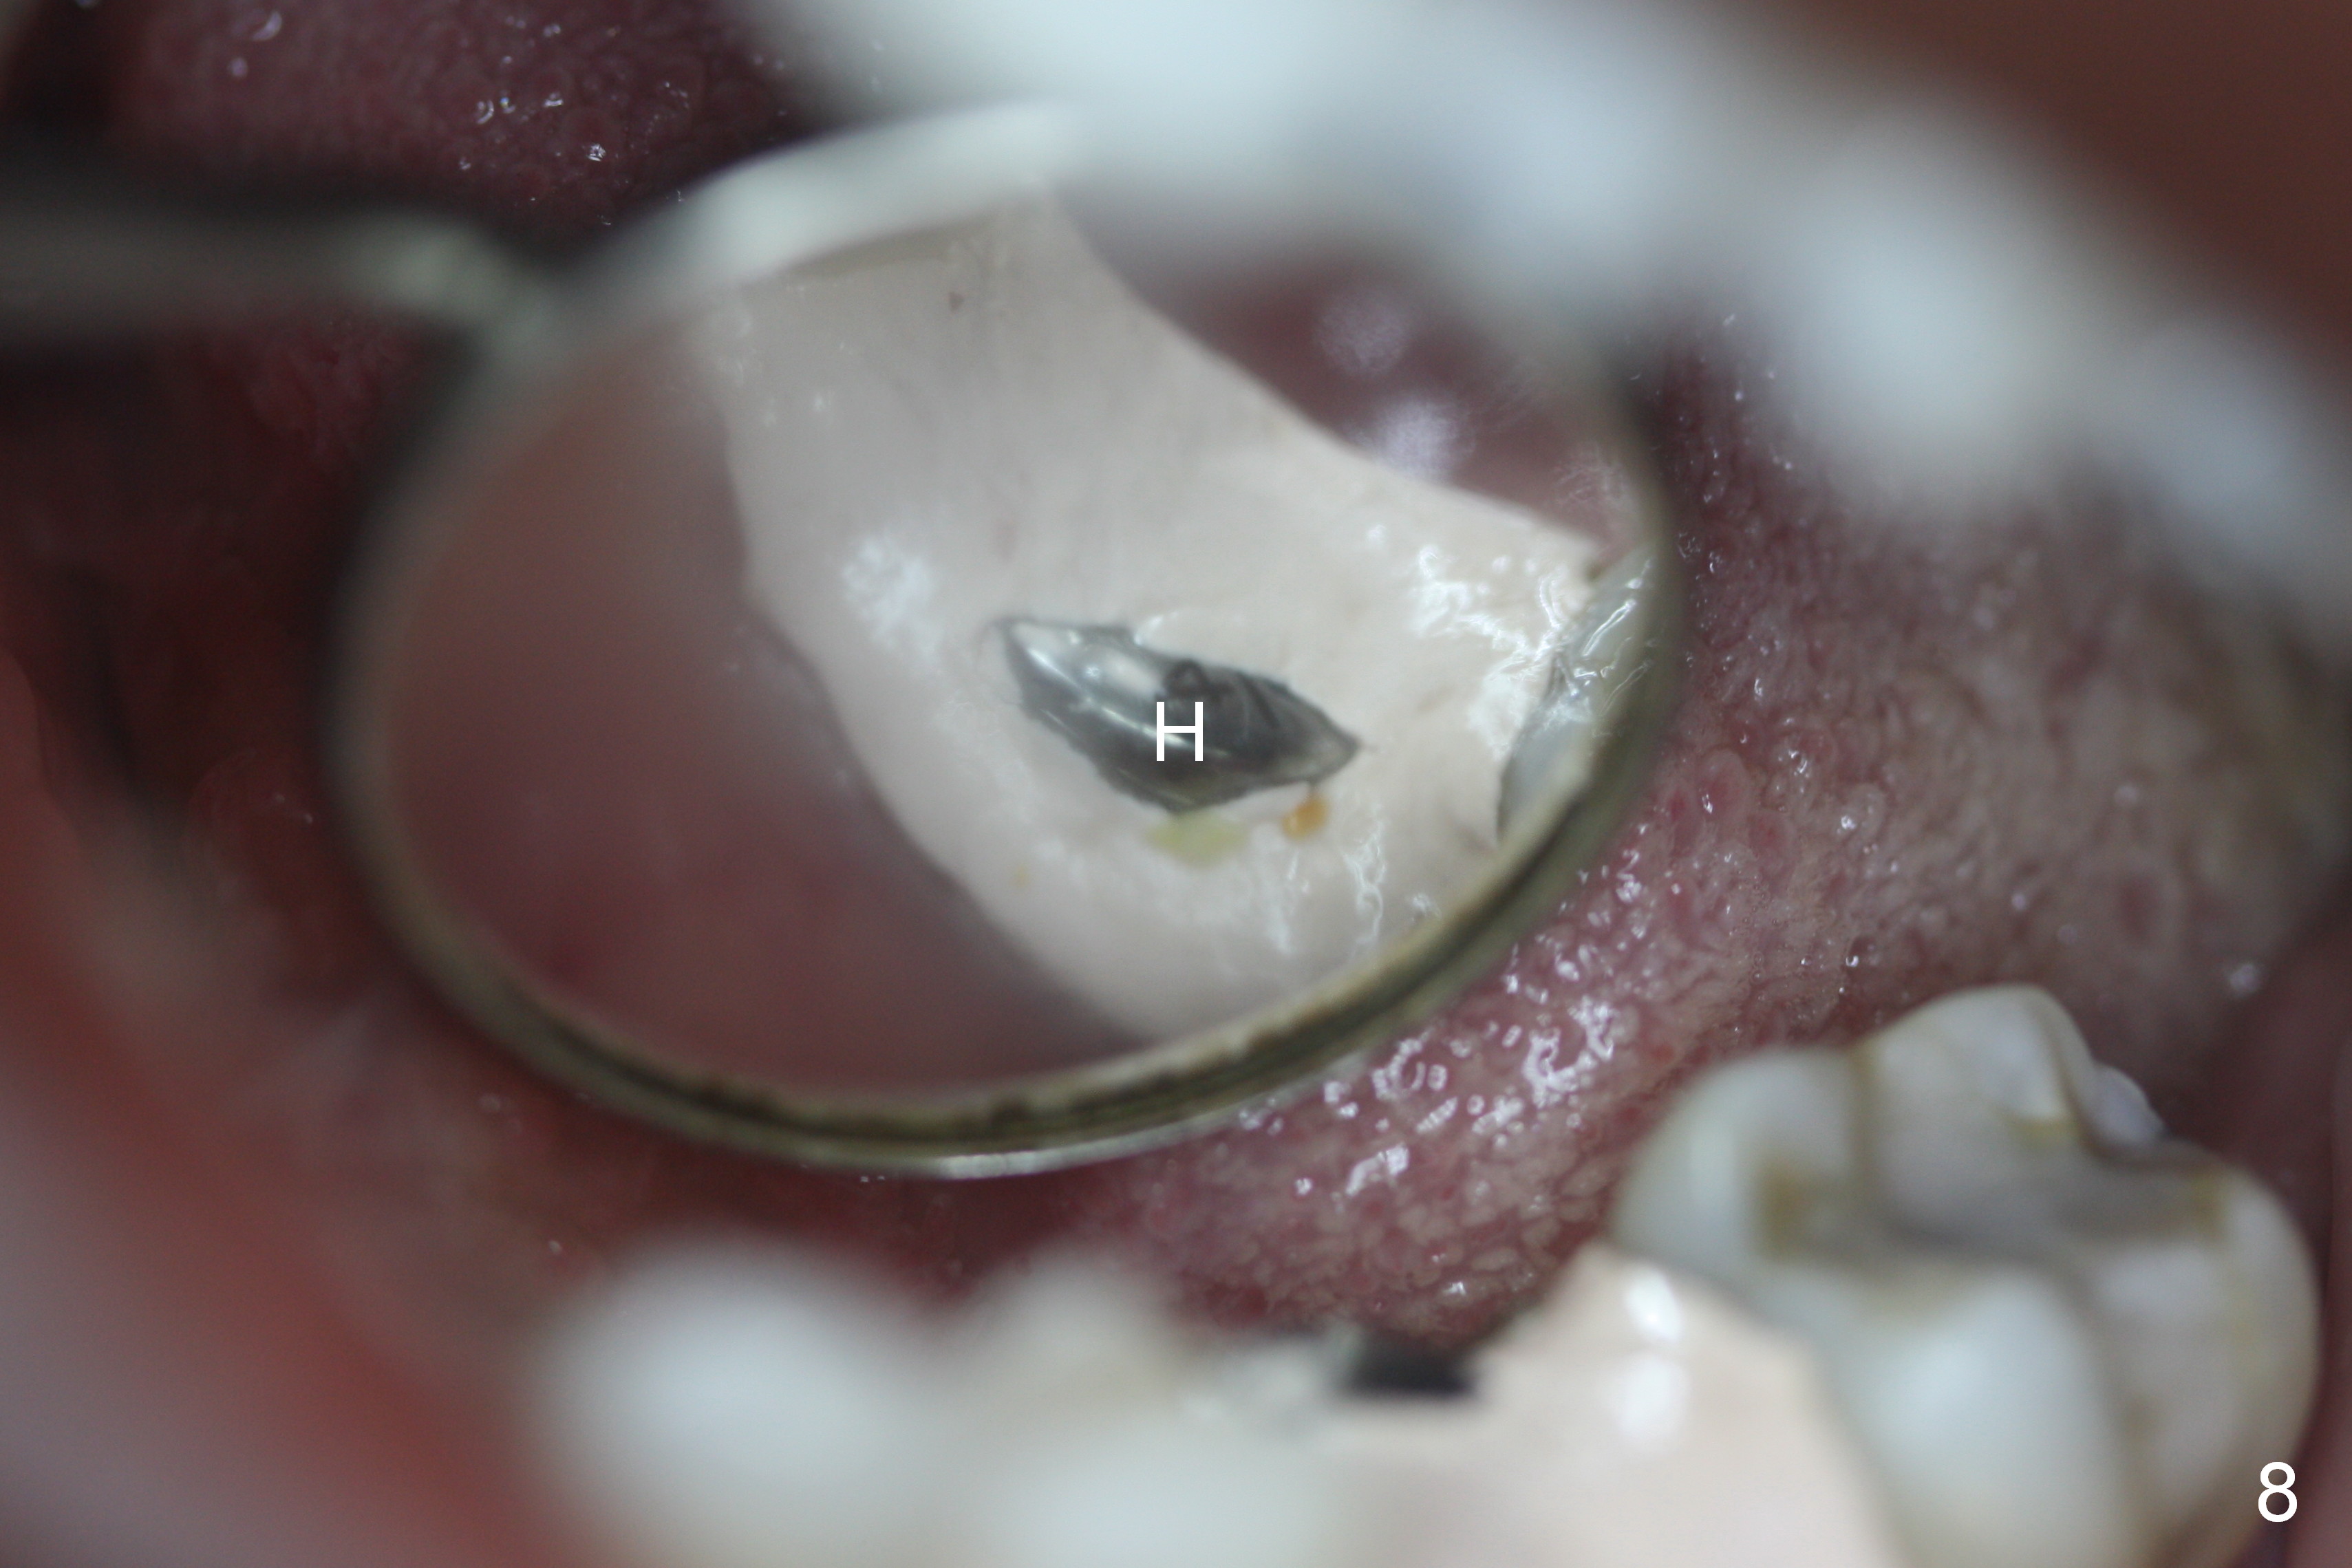

A 44-year-old black lady is a typical dental phobic. She has lost #19 for years with history of traumatic extraction. The ridge is atrophic (Fig.1). She is not comfortable with intraoral X-ray. So CBCT is taken. The coronal section shows that the bone density is low in the coronal ridge (Fig.2 arrowheads). It is difficult to determine the buccolingual width at crest; probably a 5.9x10 mm implant is appropriate (Fig.3). The most useful information from CT is height determination for the implant (Fig.4). The initial osteotomy depth is 10 mm (Fig.5); there is a large safety margin. There is a 2 mm clearance when a 4.5x12 mm implant is placed (Fig.6). Incision is sutured; a 8x4 (3) mm healing abutment is placed (Fig.7 arrowhead), followed by application of perio dressing. The latter remains stable 13 days postop thanks to the holding effect of the healing abutment (Fig.8 H). The wound has apparently healed when the dressing is removed (Fig.9). It appears that the edentulous space is extremely wide. The 4.5 mm implant may not sustain masticatory force. Limited orthodontic treatment appears to be necessary, using the implant as an anchorage to move the neighboring teeth (Fig.10 arrows). In fact the orthodontic treatment is not rendered. A crown is cemented 14 months postop. The cortical bone is thickened around the implant 15 months post cementation (Fig.11).